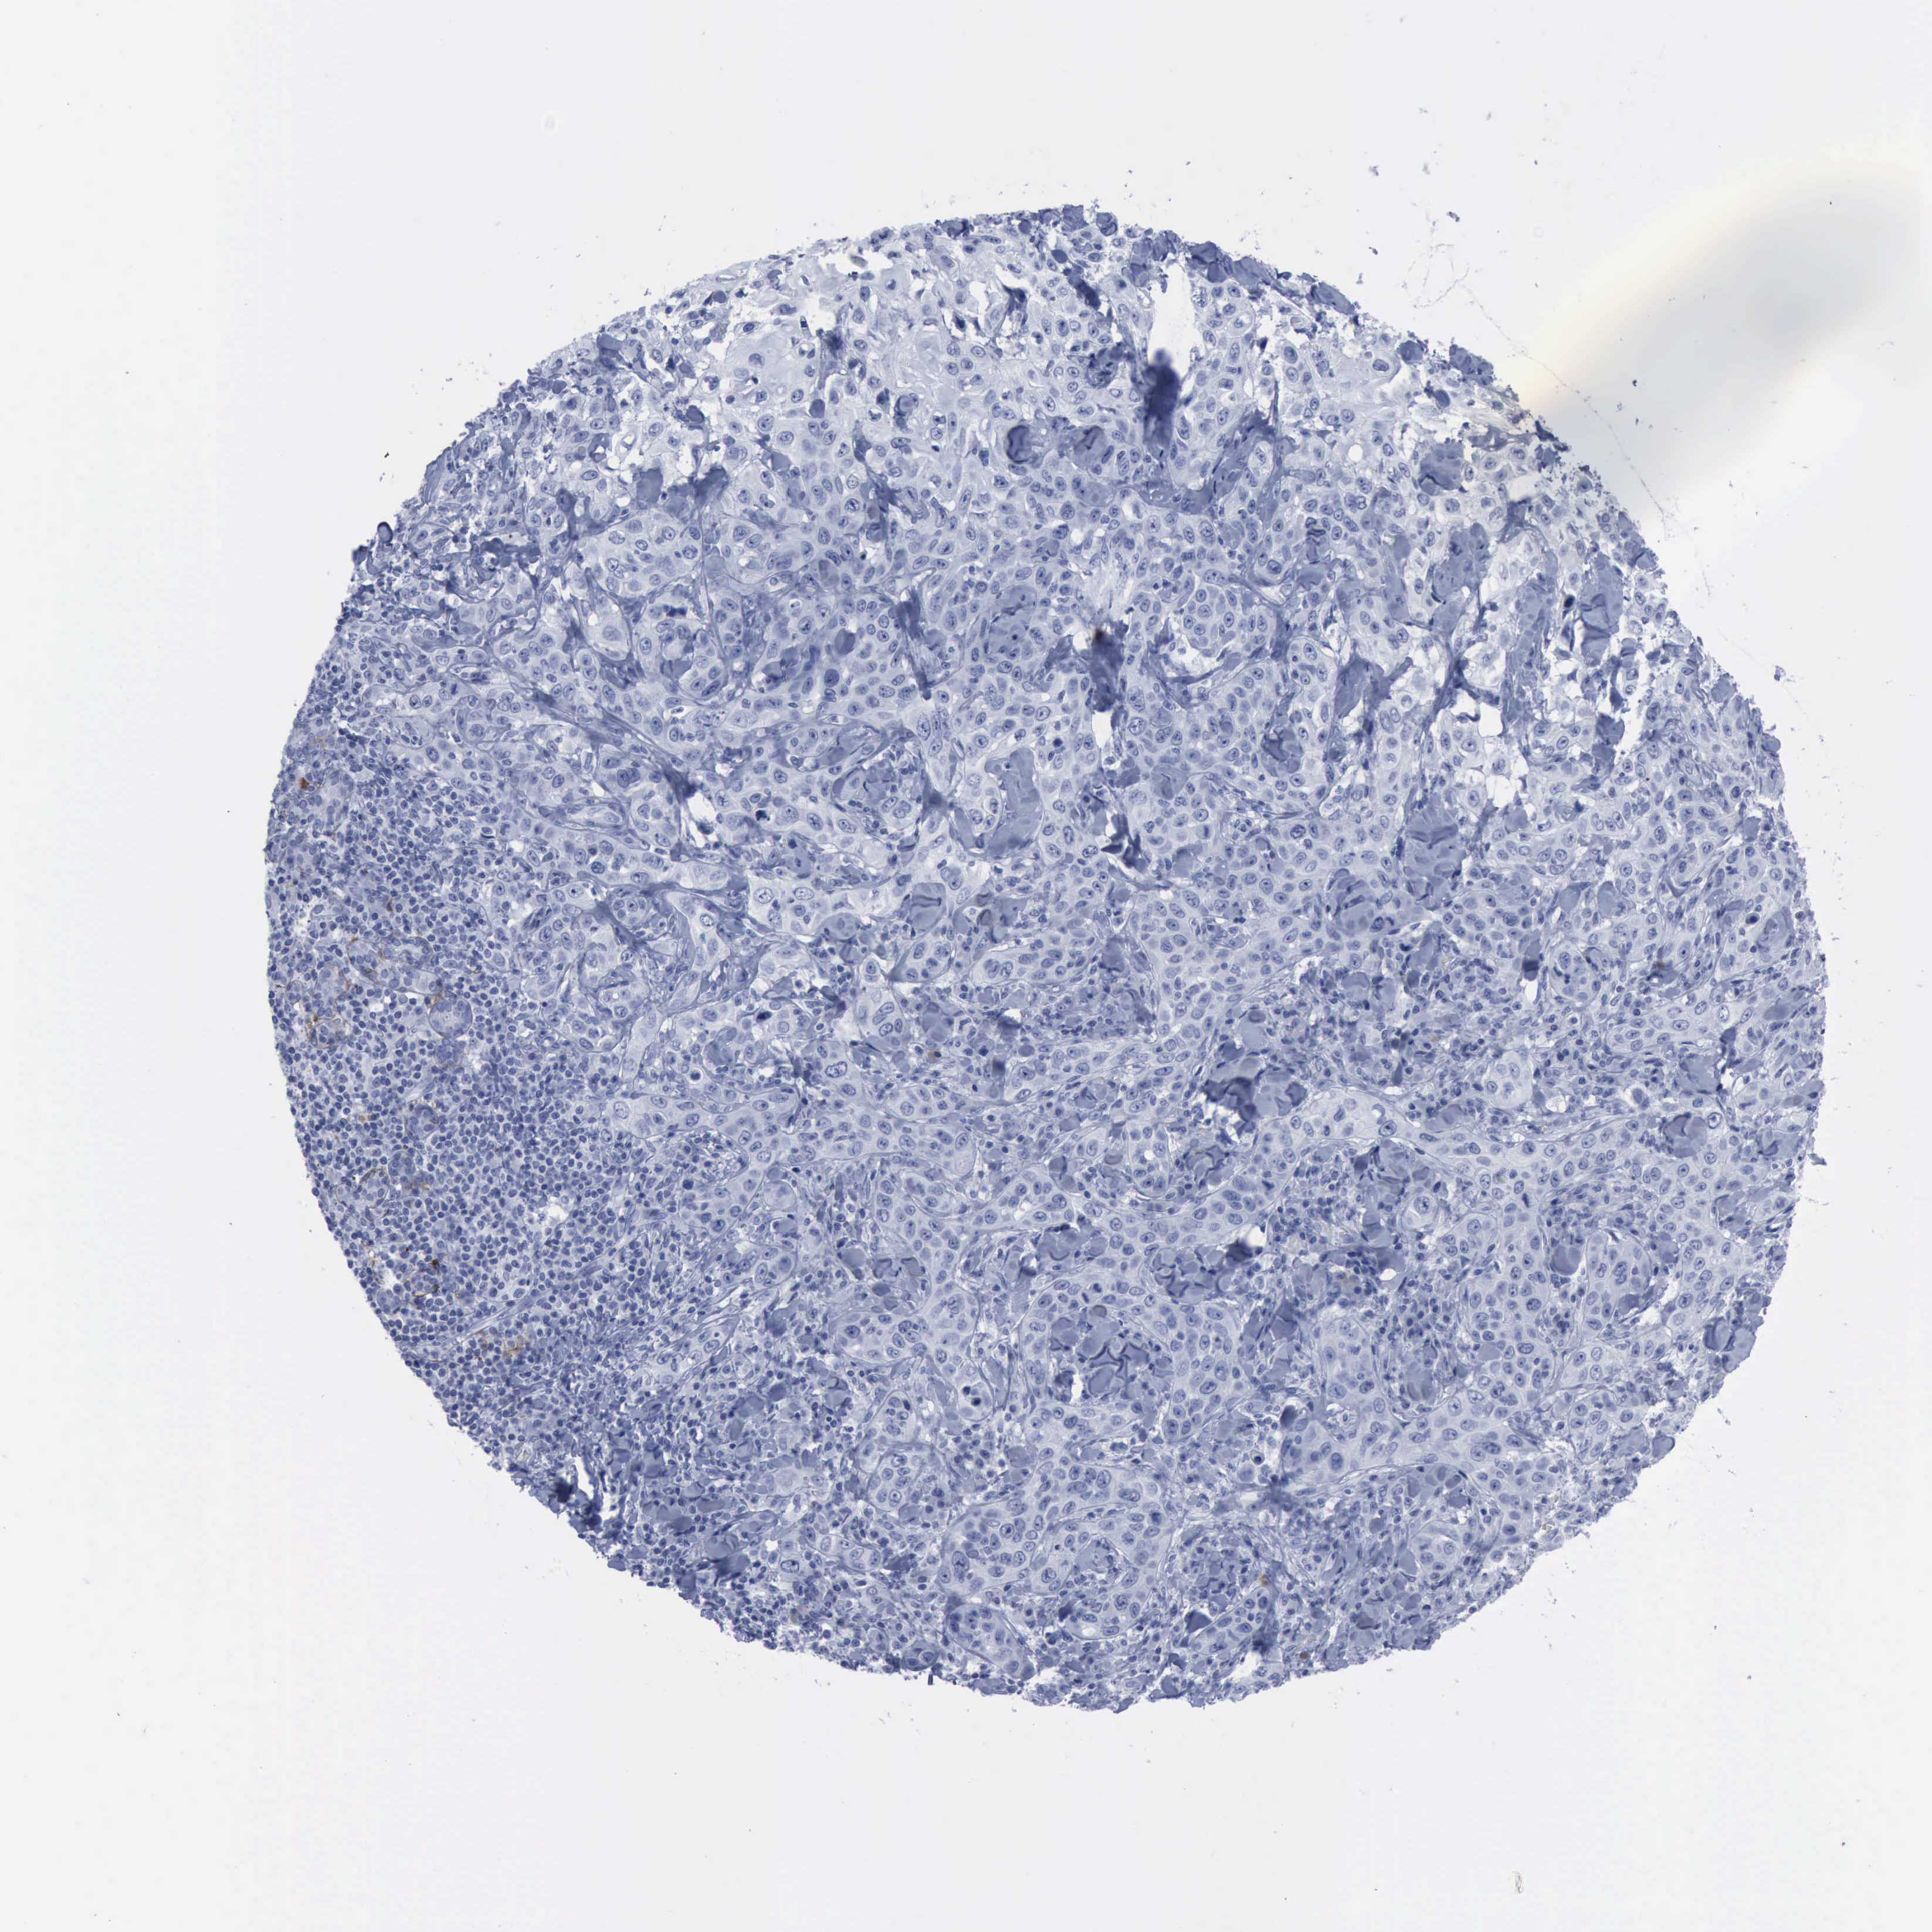

SKIN CANCER - Protein expressioni

A mouse-over function shows sample information and annotation data. Click on an image to view it in a full screen mode. Samples can be filtered based on level of antibody staining by selecting one or several of the following categories: high, medium, low and not detected. The assay and annotation is described here.

Antibody stainingi

Antibody staining in the annotated cell types in the current human tissue is reported as not detected, low, medium, or high, based on conventional immunohistochemistry profiling in selected tissues. This score is based on the combination of the staining intensity and fraction of stained cells.

Each image is clickable and will lead to virtual microscopy that enables deeper exploration of all samples and also displays staining intensity scores, fraction scores and subcellular localization as well as patient and tissue information for each sample.

Antibody HPA004765

Antibody CAB000143

Antibody CAB001995

Staining

High

Medium

Low

Not detected

Intensity

Strong

Moderate

Weak

Negative

Quantity

>75%

75%-25%

<25%

None

Location

Nuclear

Cytoplasmic/membranous

Cytoplasmic/membranous,nuclear

Squamous cell carcinoma, NOS

Basal cell carcinoma